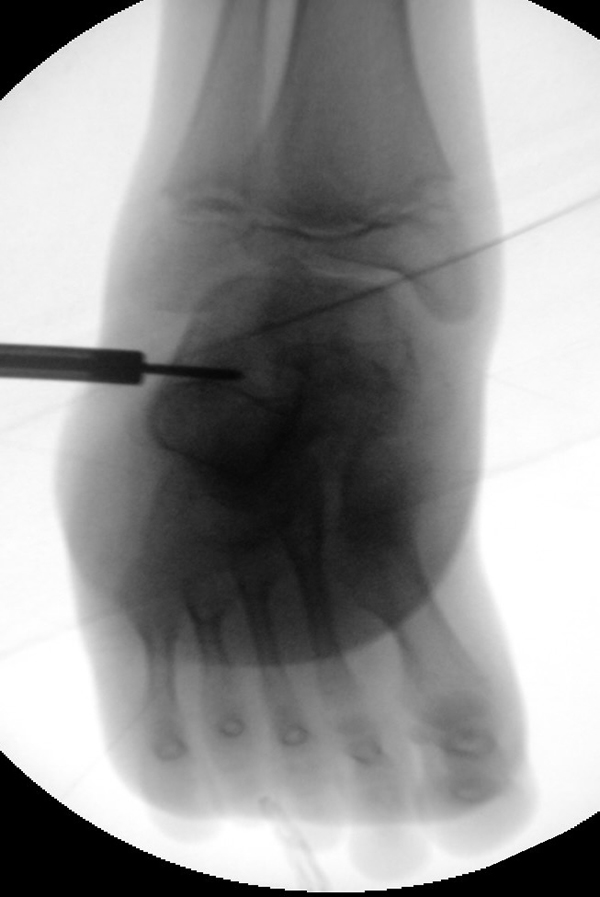

Zusätzlich schränken Wachstumsfugen die Wahl der Osteosynthese ein. Eine die Fuge kreuzende Osteosynthese ist ausschließlich mit Kirschner-Drähten möglich (Abb. 3).

Abb. 3 a-j: Beispiel einer Calcaneusverschiebeosteotomie mit offenen Wachstumsfugen und der entsprechenden Osteosynthese mit Kirschner Drähten. Lokalisation der Osteotomie (a), Lage der Fräse (b-d), Drahtlage mehrere Ansichten (e-h), Heilung der Osteotomie 4 Wochen postoperativ und Entfernung der Drähte (i-j).

Zum Lesen der Bildbeschreibung und zur Vollansicht bitte die Bilder anklicken. Bilder: A. Helmers.